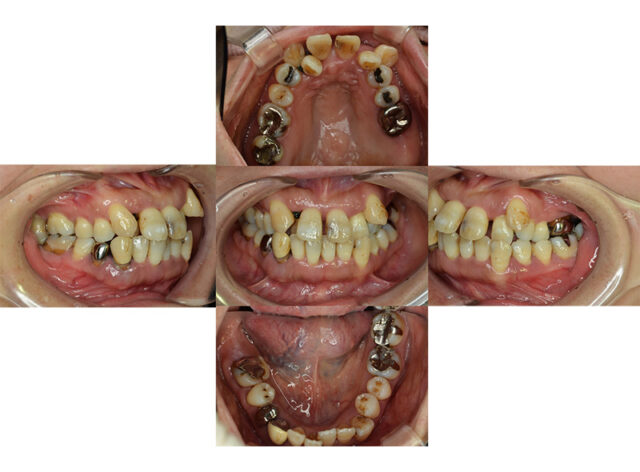

歯周再生療法 精密根管治療 歯周矯正治療 ジルコニアセラミック治療

審美歯科